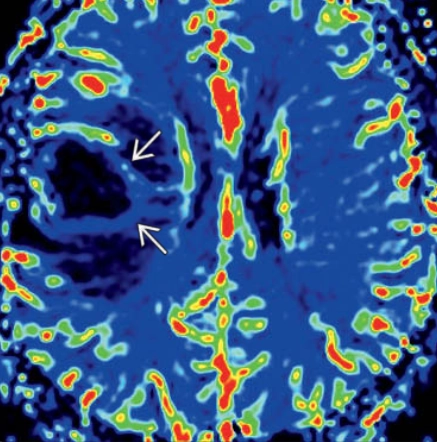

U lympho nội mạch (Intravascular (angiocentric) lymphoma - IVL)